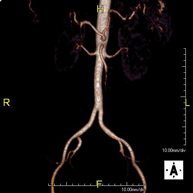

Prova diagnòstica no invasiva que consisteix en l'estudi vascular del sector aorto-ilíac i dels vasos arterials de les dues extremitats inferiors, am l'obtenció d'imatges d'alta definició anatòmica mitjançant l'ús d'un camp electromagnètic i ones de ràdio (amb un emissor i un receptor). És indispensable l'ús de contrast paramagnètic (Gadolini). No obstant, no utilitza radiació ionitzant. La qualitat de les imatges permet realitzar reconstruccions en 2D i 3D. Està especialment indicat en aquells pacients en els que hi ha sospita de malaltia vascular a les dues extremitats, en pacients amb malaltia vascular de les dues extremitats com a mapa vascular abans del tractament (percutani o quirúrgic), com a mapa vascular prequirúrgic en pacients amb lesions òssies o musculars que requereixin cirurgia, etc. - Angio-RM d'Artèries renals

Prova diagnòstica no invasiva que consisteix en l'estudi de l'artèria aorta abdominal per obtenir imatges d'alta definició anatòmica mitjançant l'ús d'un camp electromagnètic i ones de ràdio (amb un emissor i un receptor). És indispensable l'ús de contrast intravenós paramagnètic (Gadolini). No obstant, no utilitza radiació ionitzant. La qualitat de les imatges permet realitzar reconstruccions en 2D i 3D. Està especialment indicada en pacients amb sospita de malaltia vascular de les dues extremitats, en pacients amb malaltia vascular de les dues extremitats com a mapa vascular abans del tractament (percutani o quirúrgic), com a mapa vascular prequirúrgic en pacients amb lesions òssies o musculars que requereixin cirurgia, etc. - Angio-RM Lesió de parts toves